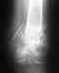

Здравствуйте! 17 декабря 2014 года в результате прыжка с высоты около 2,5 метров повредил ногу. Рентген показал оскольчатый перелом пяточной кости со смещением.

В стационаре не лежал, лечение амбулаторное, почти полтора месяца, нога в гипсе.Только недавно травматолог объявил, что лечение нужно было проходить в стационаре и делать вытяжку, а теперь якобы поздно и сделать уже ничего нельзя, высказав приговор - что никогда не срастется. Убедительно прошу Вас посоветовать, что в такой ситуации необходимо предпринять, возможна операция или что то другое. Снимки прилагаю. Заранее спасибо.